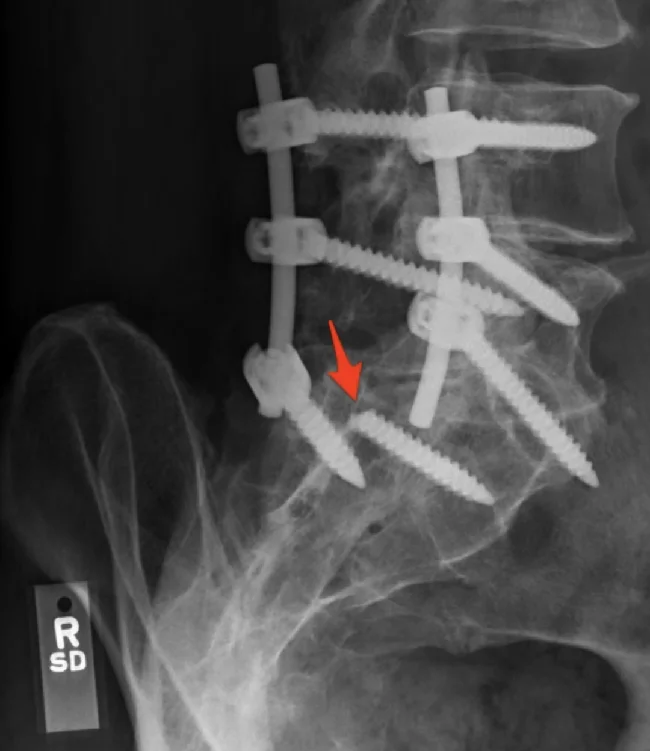

9. Один из винтов, которые удерживали позвоночник, сломался. Опять операция